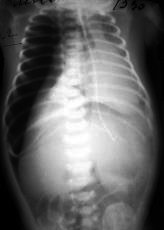

Ребенок Б. поступил в отделение реанимации новорожденных НОДКБ 12.05.2017 на вторые сутки жизни (дата рождения 11.05.17). Доставлен неонатальной реанимационной бригадой Центра медицины катастроф из Центральной районной больницы (230 км от Нижнего Новгорода) с диагнозом: синдром дыхательных расстройств, дыхательная недостаточность I степени, перинатальное поражение ЦНС, синдром угнетения. Ребенок от пятой беременности, третьих преждевременных родов на сроке 36 нед. гестации, вес при рождении 2110 г, оценка по шкале Апгар 3/6 баллов. Проводились реанимационные мероприятия: санация верхних дыхательных путей, ИВЛ мешком Амбу, после чего ребенок закричал. От кислорода зависим с первых суток жизни. При поступлении: состояние тяжелое, дотация кислорода через маску, гипотония, гипорефлексия, дыхание с участием вспомогательной мускулатуры, ослабленное с обеих сторон. Тоны сердца приглушены. При рентгенографии легких при поступлении – подозрение на диафрагмальную грыжу справа (рис. 6).

Рис. 6. Рентгенограмма органов грудной клетки. Признаки правосторонней диафрагмальной грыжи.